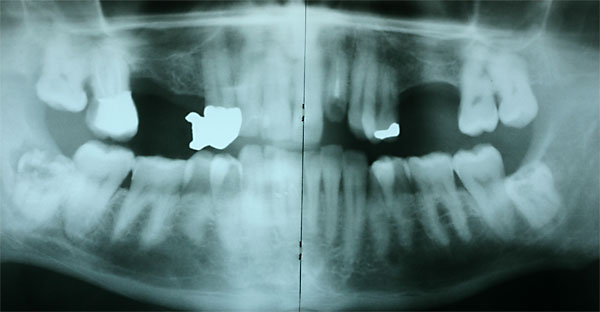

FOTO Ausgangsröntgenbild |

Fall: festsitzender Zahnersatz im Oberkiefer auf 8 Implantaten